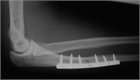

1. 尺骨骨折があった場合、橈骨頭脱臼を見流さないことがポイントである。

1. 見逃された陳旧例では前腕の回旋運動と肘の屈伸運動が障害される可能性があるため、できるだけ早く専門医に紹介する。